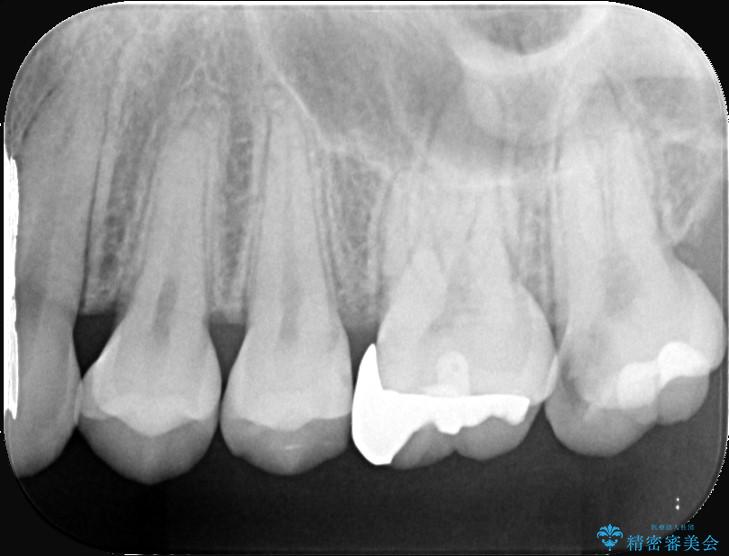

精密検査の結果、非常に深い虫歯があり、通常であれば抜髄が必要な状態でした。

しかし、神経を抜くと歯の寿命が縮まってしまうため、今回は神経の一部を温存する部分的断髄法(VPT)を提案しました。

高い殺菌性と封鎖性、そして組織の再生を促す効果を持つMTAセメントを使用して神経を保護し、最終的には強度と審美性に優れたセラミックで修復する計画を立案しました。

部分的断髄法(MTAの使用): ラバーダム防湿を行い、無菌的な環境下で虫歯を慎重に除去。神経の露出を確認した後、炎症を起こしている一部の神経のみを除去し、残りの健全な神経を保護するためにMTAセメントを充填しました。これにより、神経の機能を維持し、歯を内部から守ることが可能となりました。